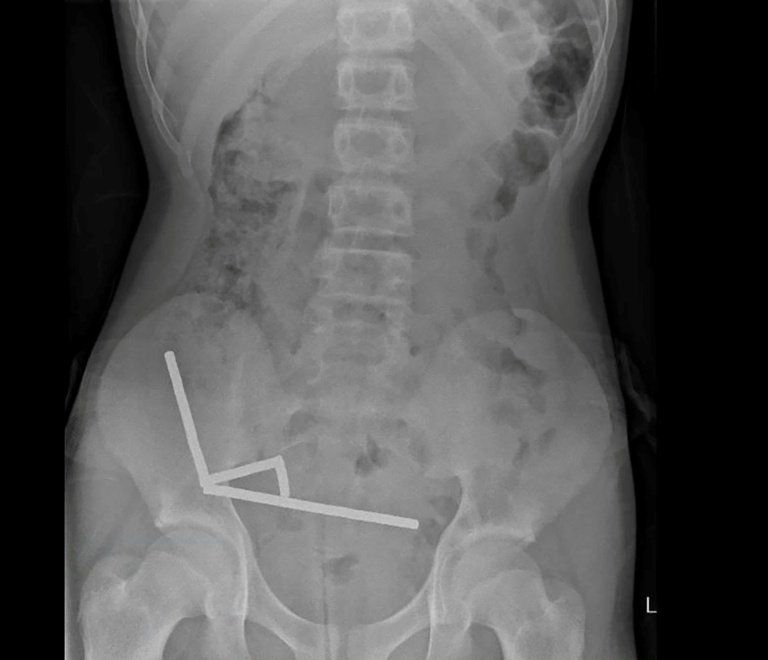

Un adolescent de treize ans a été hospitalisé d’urgence à Tauranga, sur l’île du Nord de la Nouvelle-Zélande, après avoir présenté des douleurs abdominales persistantes durant plusieurs jours. Les examens médicaux ont révélé la présence d’environ quatre-vingt à cent aimants au néodyme, d’environ cinq millimètres sur deux, agrégés dans son système digestif. Le jeune patient a reconnu avoir ingéré ces objets une semaine avant son admission à l’hôpital.

Selon le compte-rendu clinique publié dans le New Zealand Medical Journal, les aimants avaient provoqué des lésions tissulaires importantes dans quatre sections distinctes de l’intestin grêle et du côlon. La compression exercée par ces éléments a entraîné la nécrose de plusieurs zones, nécessitant une résection chirurgicale. Les médecins ont procédé à l’ablation des aimants et des tissus non viables lors d’une opération qui a permis la stabilisation de l’état du patient.